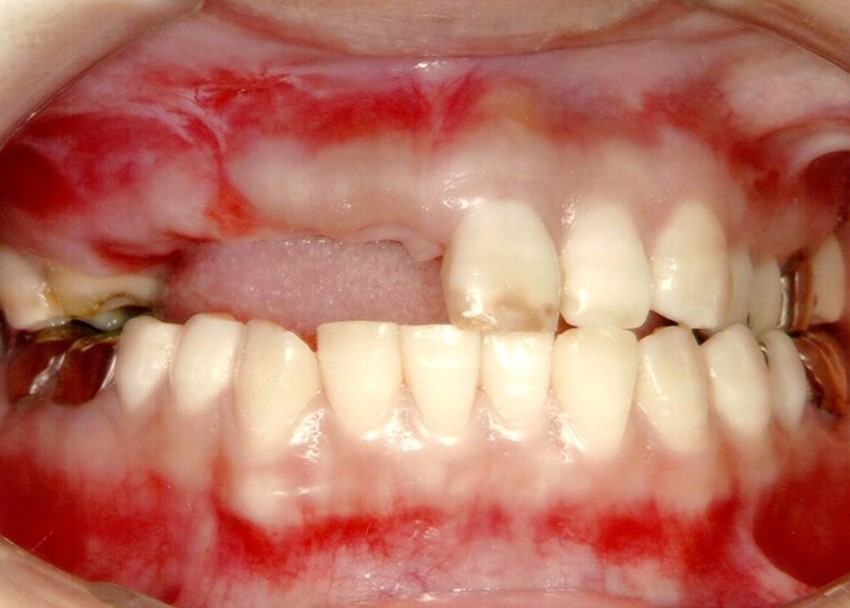

ブリッジの欠点

少ない本数の土台で支えるブリッジの場合、過重負担のため、支える歯がむし歯や歯槽膿漏で悪くなると、ブリッジ全て失う可能性があります。

特に保険で作られた適合があまいブリッジは約7年で50%が悪くなります。

少ない本数で支えられ作られたブリッジ、見た目はよいですが…

少ない支えで過重負担となり、支える歯ごと抜けてしまいました。

その結果、多数の歯を一度に失うことになりました。